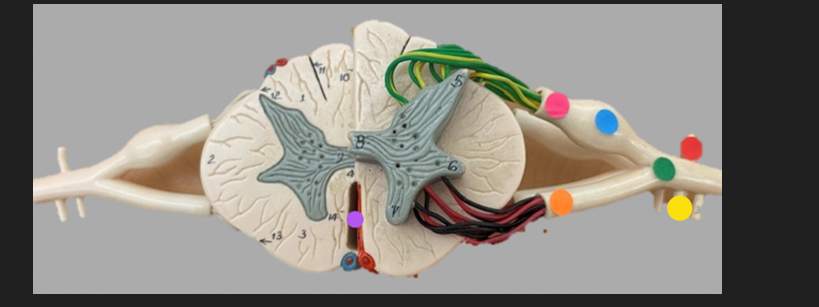

green dot

spinal nerve

orange dot

ventral root

pink dot

dorsal root

blue dot

dorsal root ganglion

red dot

dorsal ramus

yellow dot

ventral ramus

purple dot

anterior median fissure

red dot

posterior (dorsal) horn

purple dot

lateral horn

dark blue dot

anterior (ventral) horn

orange dot

dorsal column

yellow dot

lateral column

dark green

anterior column

line green and pink doit

gray commissure

light blue dot

posterior median sulcus